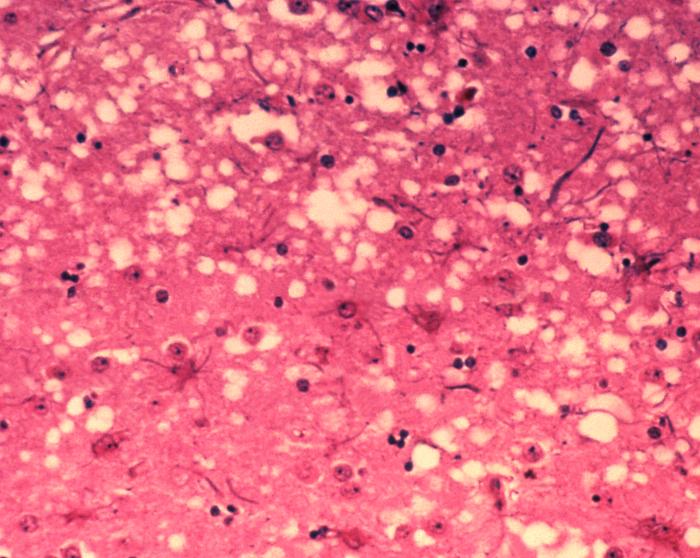

Prion disease is an umbrella term for a group of fatal and currently untreatable neurodegenerative diseases that not only affect humans, but also wild and captive animals. These diseases include Creutzfeldt-Jakob disease (CJD) in humans, bovine spongiform encephalopathy (BSE, or “mad cow disease”), and chronic wasting disease (CWD) affecting deer, elk and moose.

The central event in these diseases is the conversion of the prion protein (PrPC) from its normal shape into a pathological structure (PrPSc) that is toxic to neurons and can replicate itself through binding to unconverted PrPC molecules. This ability to self-replicate makes these misfolded proteins infectious, which has enormous implications for public health.